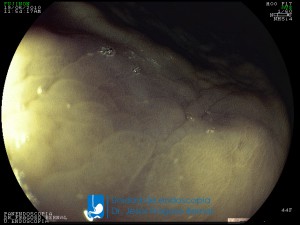

La Unidad de Endoscopía fue creada en 2002 por el Dr. Jesús Fragoso Bernal, es pionera en el estado por la utilización de la tecnología más avanzada, que nos permite ofrecer servicios integrales de diagnóstico y tratamiento para las enfermedades del aparato digestivo.